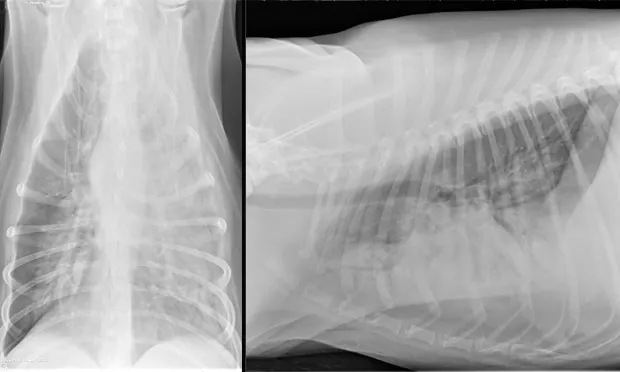

The patient recovered well and was discharged 7 days after admission. Outpatient therapy was continued with enrofloxacin at 10 mg/kg PO q24h, doxycycline at 5 mg/kg PO q12h, and amoxicillin trihydrate–clavulanate potassium (Clavamox, animalhealth.pfizer.com) at 13.75 mg/kg PO q12h 2 weeks after radiographic resolution of pneumonia (Figure 4) for a total of 7 weeks.

In follow-up films, alveolar infiltrates are completely resolved. There is a very slight increased nonstructured interstitial pattern within the left caudal lung lobe, which could be artifact as a result of mild to moderate leftward obliquity or possibly pulmonary fibrosis secondary to previous pneumonia. Courtesy Montrose Veterinary Clinic